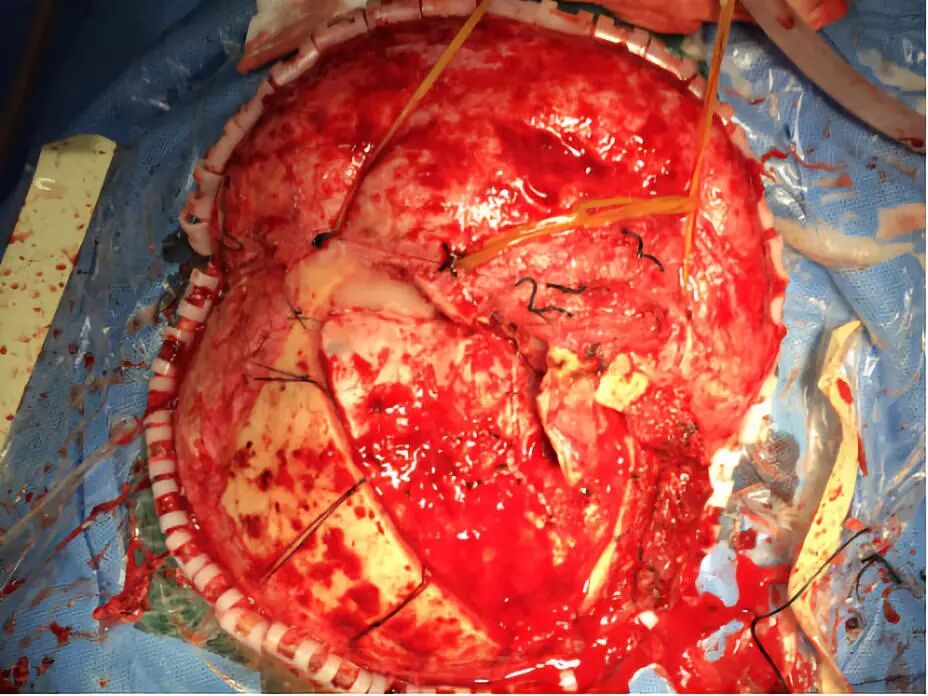

带蒂骨膜反折覆盖颅底,加固修补

复位骨瓣